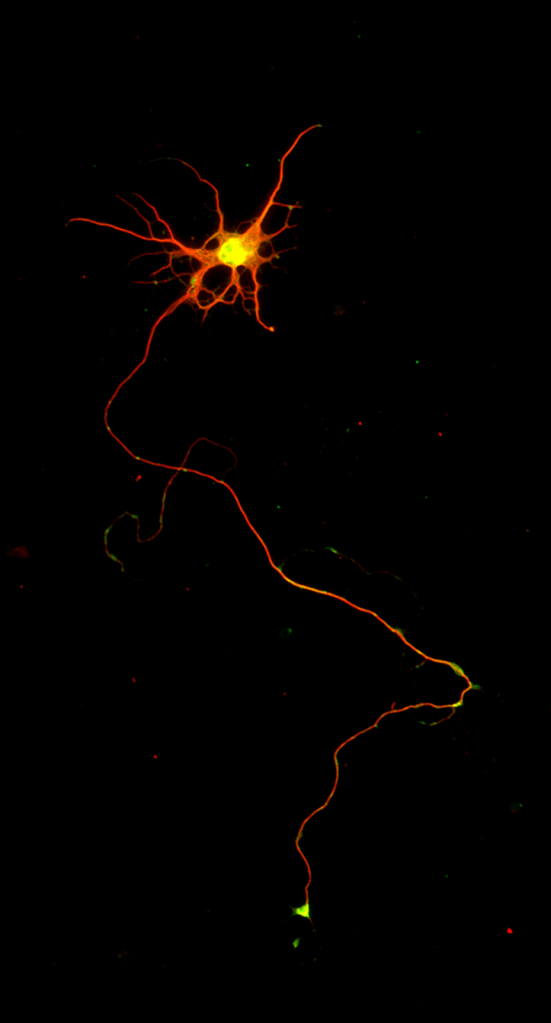

A lab-grown neuron engineered by the Macklis lab shows the cell body top extending a long axon.

Photo by Ozkan Padmanabhan

“And lo and behold,” said Macklis, “unlike anything that people have published before, they send out one long axon, and they look like the right kind of neuron.”

“And lo and behold, unlike anything that people have published before, they send out one long axon, and they look like the right kind of neuron.”

In subsequent tests, these cells bore all the morphological, molecular, electrophysiological characteristics of normal CSN cells and expressed the same genes. A separate commentary in the journal called the new approach a “perfect recipe” for making these neurons and reprogramming cells “with the goal to repair the brain.”